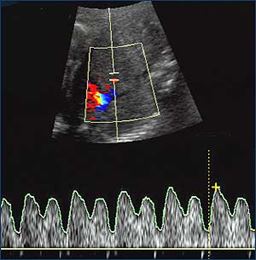

Laser ablation of placental anastomoses was pioneered in the US and has been performed for over ten years in North America and Europe. The procedure aims to treat the underlying cause of TTTS by coagulating vascular anastomoses with a laser beam. Under initial ultrasound guidance, a tiny camera is inserted through a fetoscope (a thin, flexible instrument) into the uterus. Once inserted, direct vision through the fetoscope is used first to identify the connecting vessels and second to coagulate or seal them shut. Coagulating the vessels stops the blood flow between the donor and recipient through the placenta. The coagulation is done on the surface of the placenta, in the territory between the twins, where the imbalanced blood volume sharing takes place. The umbilical cords themselves are not interfered with.

Ultrasound is used to identify the placental cord insertion of each baby (colored points).